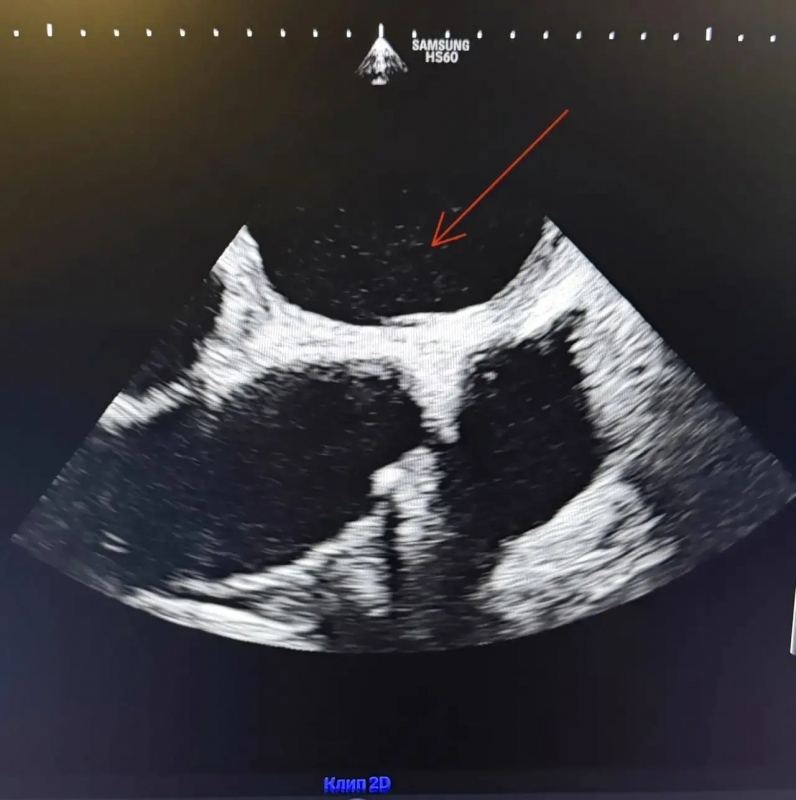

Метод прост и безопасен: пациенту вводят физраствор с микропузырьками, а затем с помощью УЗИ отслеживают их движение в сердце. Если пузырьки попадают в левое предсердие – есть дефект. Процедура занимает 10-15 минут.